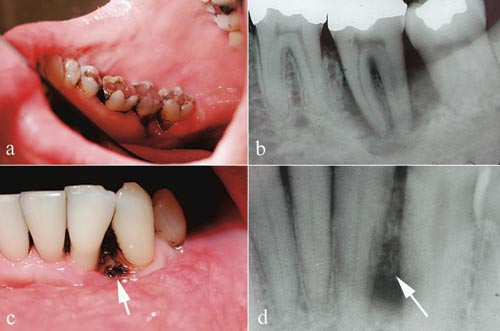

Det kliniske bildet av oral candidiasis er variert. Den vanligste uttrykksformen er pseudomembranøs og erytematøs candidiasis (fig 1a, b) som begge kan være indikasjon på sykdomsprogrediering og utvikling av AIDS (1) – (3, 6, 7). Pasientene forteller om en brennende følelse i munnen og smaksendringer. Videre ses angulær keilitt (munnviksragader med oppvekst av C albicans) hyppig hos HIV-positive personer og lar seg lett diagnostisere (fig 1c). HIV-infiserte pasienter kan også fremvise en spesiell form for gingivitt som kalles lineært gingivalt erytem (fig 1d), som er rapportert å skyldes C albicans-infeksjon (13) – (14). Denne spesielle gingivitten mistenkes også å være forløper for nekrotisk periodontitt (14) (fig 1g, fig 2).

Pseudomembranøs candidiasis (trøske) opptrer som hvite, kremaktige flekker som iblant konfluerer til tette belegg på oral mucosa (fig 1a). De hvitlige forandringene består av overvekst av sopphyfer blandet med deskvamerte epitelceller og lar seg skrape av og etterlater en rødlig, lettblødende slimhinneoverflate. Denne typen candidiasis kan opptre alle steder i munnhulen og i pharynx.

Ved erytematøs candidiasis ses en uskarpt avgrenset rødlig slimhinneoverflate av forskjellig størrelse, og iblant forekommer en intens svie og brenning (fig 1b). Oftest ses denne typen i ganen eller på tungeryggen og i kombinasjon med den pseudomembranøse typen.

Angulær keilitt opptrer som hissige, rødlige ulcerasjoner og sprekkdanning i munnviken unilateralt eller bilateralt (fig 1c).